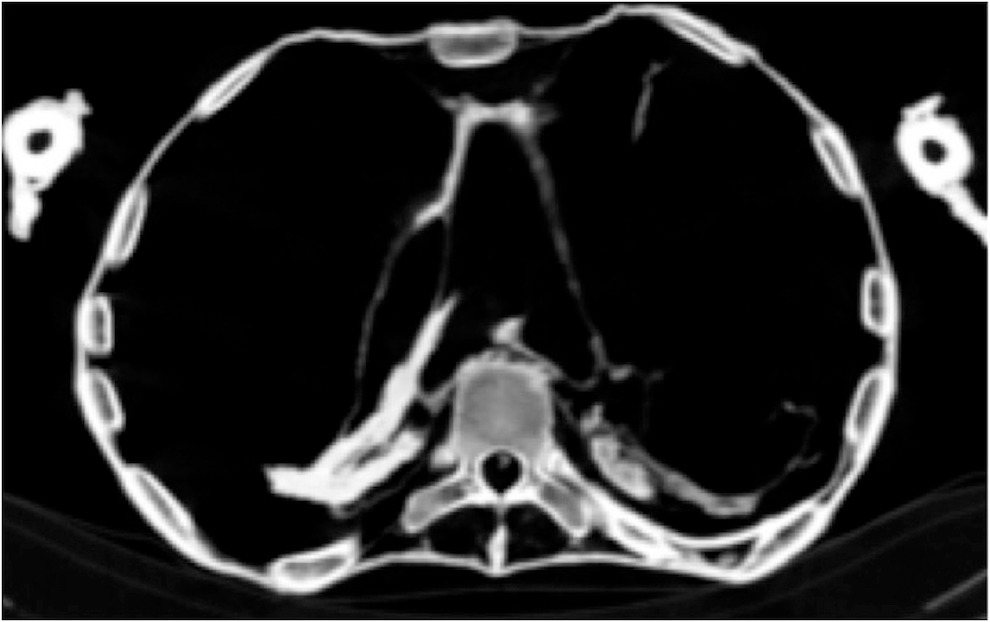

وتشير نتائج التصوير المقطعى إلى أن “مومياء المرأة غير المعروفة”، “كانت مصابة بمرض تصلب الشرايين شديد الدرجة والذى أصاب العديد من شرايين الجسد، ومرض تصلب الشرايين هو مرض تنكسى يصيب جدار الشرايين بشكل تدريجى ما يؤدى إلى ضيق فى تجويف الوعاء الدموى وانسداده، ويتم تحديد أماكن تصلب الشرايين فى فحص الأشعة المقطعية كمناطق عالية التكلس داخل جدران الشرايين والتى يمكن التعرف عليها حسب مكان الشريان.

فأثبت فحص الأشعة المقطعية لـ “مومياء المرأة غير المعروفة” أنها عانت من تصلب فى شرايين القلب التاجية الأيمن والأيسر وكذلك شرايين الرقبة وشريان الأبهر البطنى والحرقفى وكذلك شرايين الطرفين السفليين والساقين.

و تفترض هذه الدراسة أن الأميرة ماتت فجأة بنوبة قلبية وهى على وضع الجسد الحالى ساقاها مثنية وملتفة عند الكاحل، وتسبب الموت فى ميل الرأس إلى الجانب الأيمن وارتخاء عضلات الفك مما أدى إلى فتح الفم، و تشير الدلائل أن المتوفاه ظلت لفترة كافية لعدة ساعات على هذه الوضعية قبل أن يتم اكتشاف الجثمان فأدى التشنج الذى يعقب الموت إلى تيبس العضلات والمفاصل وإبقاء مومياء الأميرة على وضعية الوفاة هذه فلم يتمكن المحنطون من تأمين إغلاق الفم أو وضع الجسد فى حالة الاستلقاء كما كان المعتاد مع باقى المومياوات، فيبدو أنه لم يهمل المحنطون عملهم عن عمد و لكن ظروف الوفاة أدت لوضعية المومياء هذه والغير معتادة، وأظهرت صور فحص الأشعة المقطعية أن المحنطون لم يستخرجوا مخ المومياء، حيث لا يزال يرى المخ بداخل تجويف الجمجمة ولكنه يميل إلى الجانب الأيمن وذلك لوضعية الجسد على هذا الجانب عند الموت و بعد التحنيط.